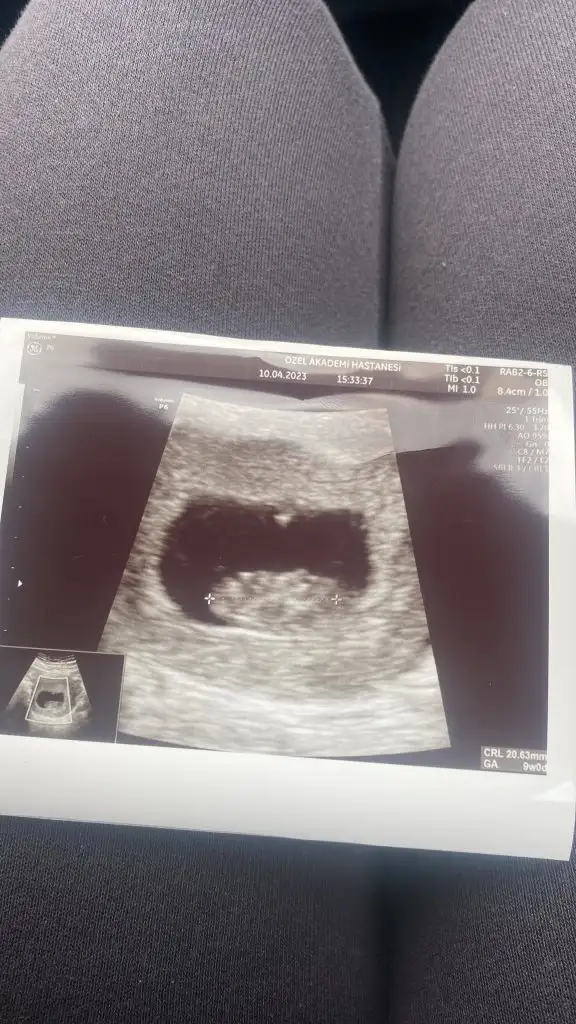

Bana da yorum yapabilir misiniz 9.hafta karındanKarından görüntüyse erkek vajinal görüntüyse kız :)

Karındansa kız vajinal görüntüyse erkek :)Bana da yorum yapabilir misiniz 9.hafta karından

Şöyle burda bebek ve plesantası çok ortada çıkmış maalesef anlayamadım. Sağda olunca kız solda olunca erkek oluyor karından ultrasondaBu da 10 haftalık hali hala kız mı diyorsunuz peki ?ManyakPrenses

Selam canim banada bakarmisin 9 haftalik karindan ultrasonTeşekkür ederim Amin İnşallah

Merhaba karından ultrasonda erkek vajinalse kız canım